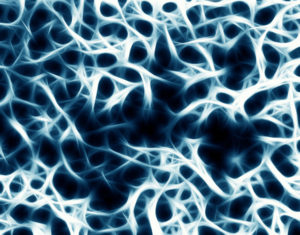

Unter Osteoporose versteht man eine Stoffwechselerkrankung der Knochen, die durch eine Abnahme der Knochenmasse und eine Verschlechterung der Architektur des Knochengewebes charakterisiert ist, wodurch es zu einer Abnahme der Knochenstabilität und zu einem erhöhten Knochenbruchrisiko kommt.

Unter Osteoporose versteht man eine Stoffwechselerkrankung der Knochen, die durch eine Abnahme der Knochenmasse und eine Verschlechterung der Architektur des Knochengewebes charakterisiert ist, wodurch es zu einer Abnahme der Knochenstabilität und zu einem erhöhten Knochenbruchrisiko kommt.

mechanischen Belastungsreize, wird Knochenmasse abgebaut. Regelmäßiges Muskeltraining wirkt aufgrund der Zug- und Druckbelastungen als Reiz (funktionell bzw. formativ) auf die Knochen. Dadurch kommt es zu einer vermehrten Mineralisierung des Knochens, einer Verstärkung der Knochenbälkchenstruktur und einer Dickenzunahme der Knochenrinde.